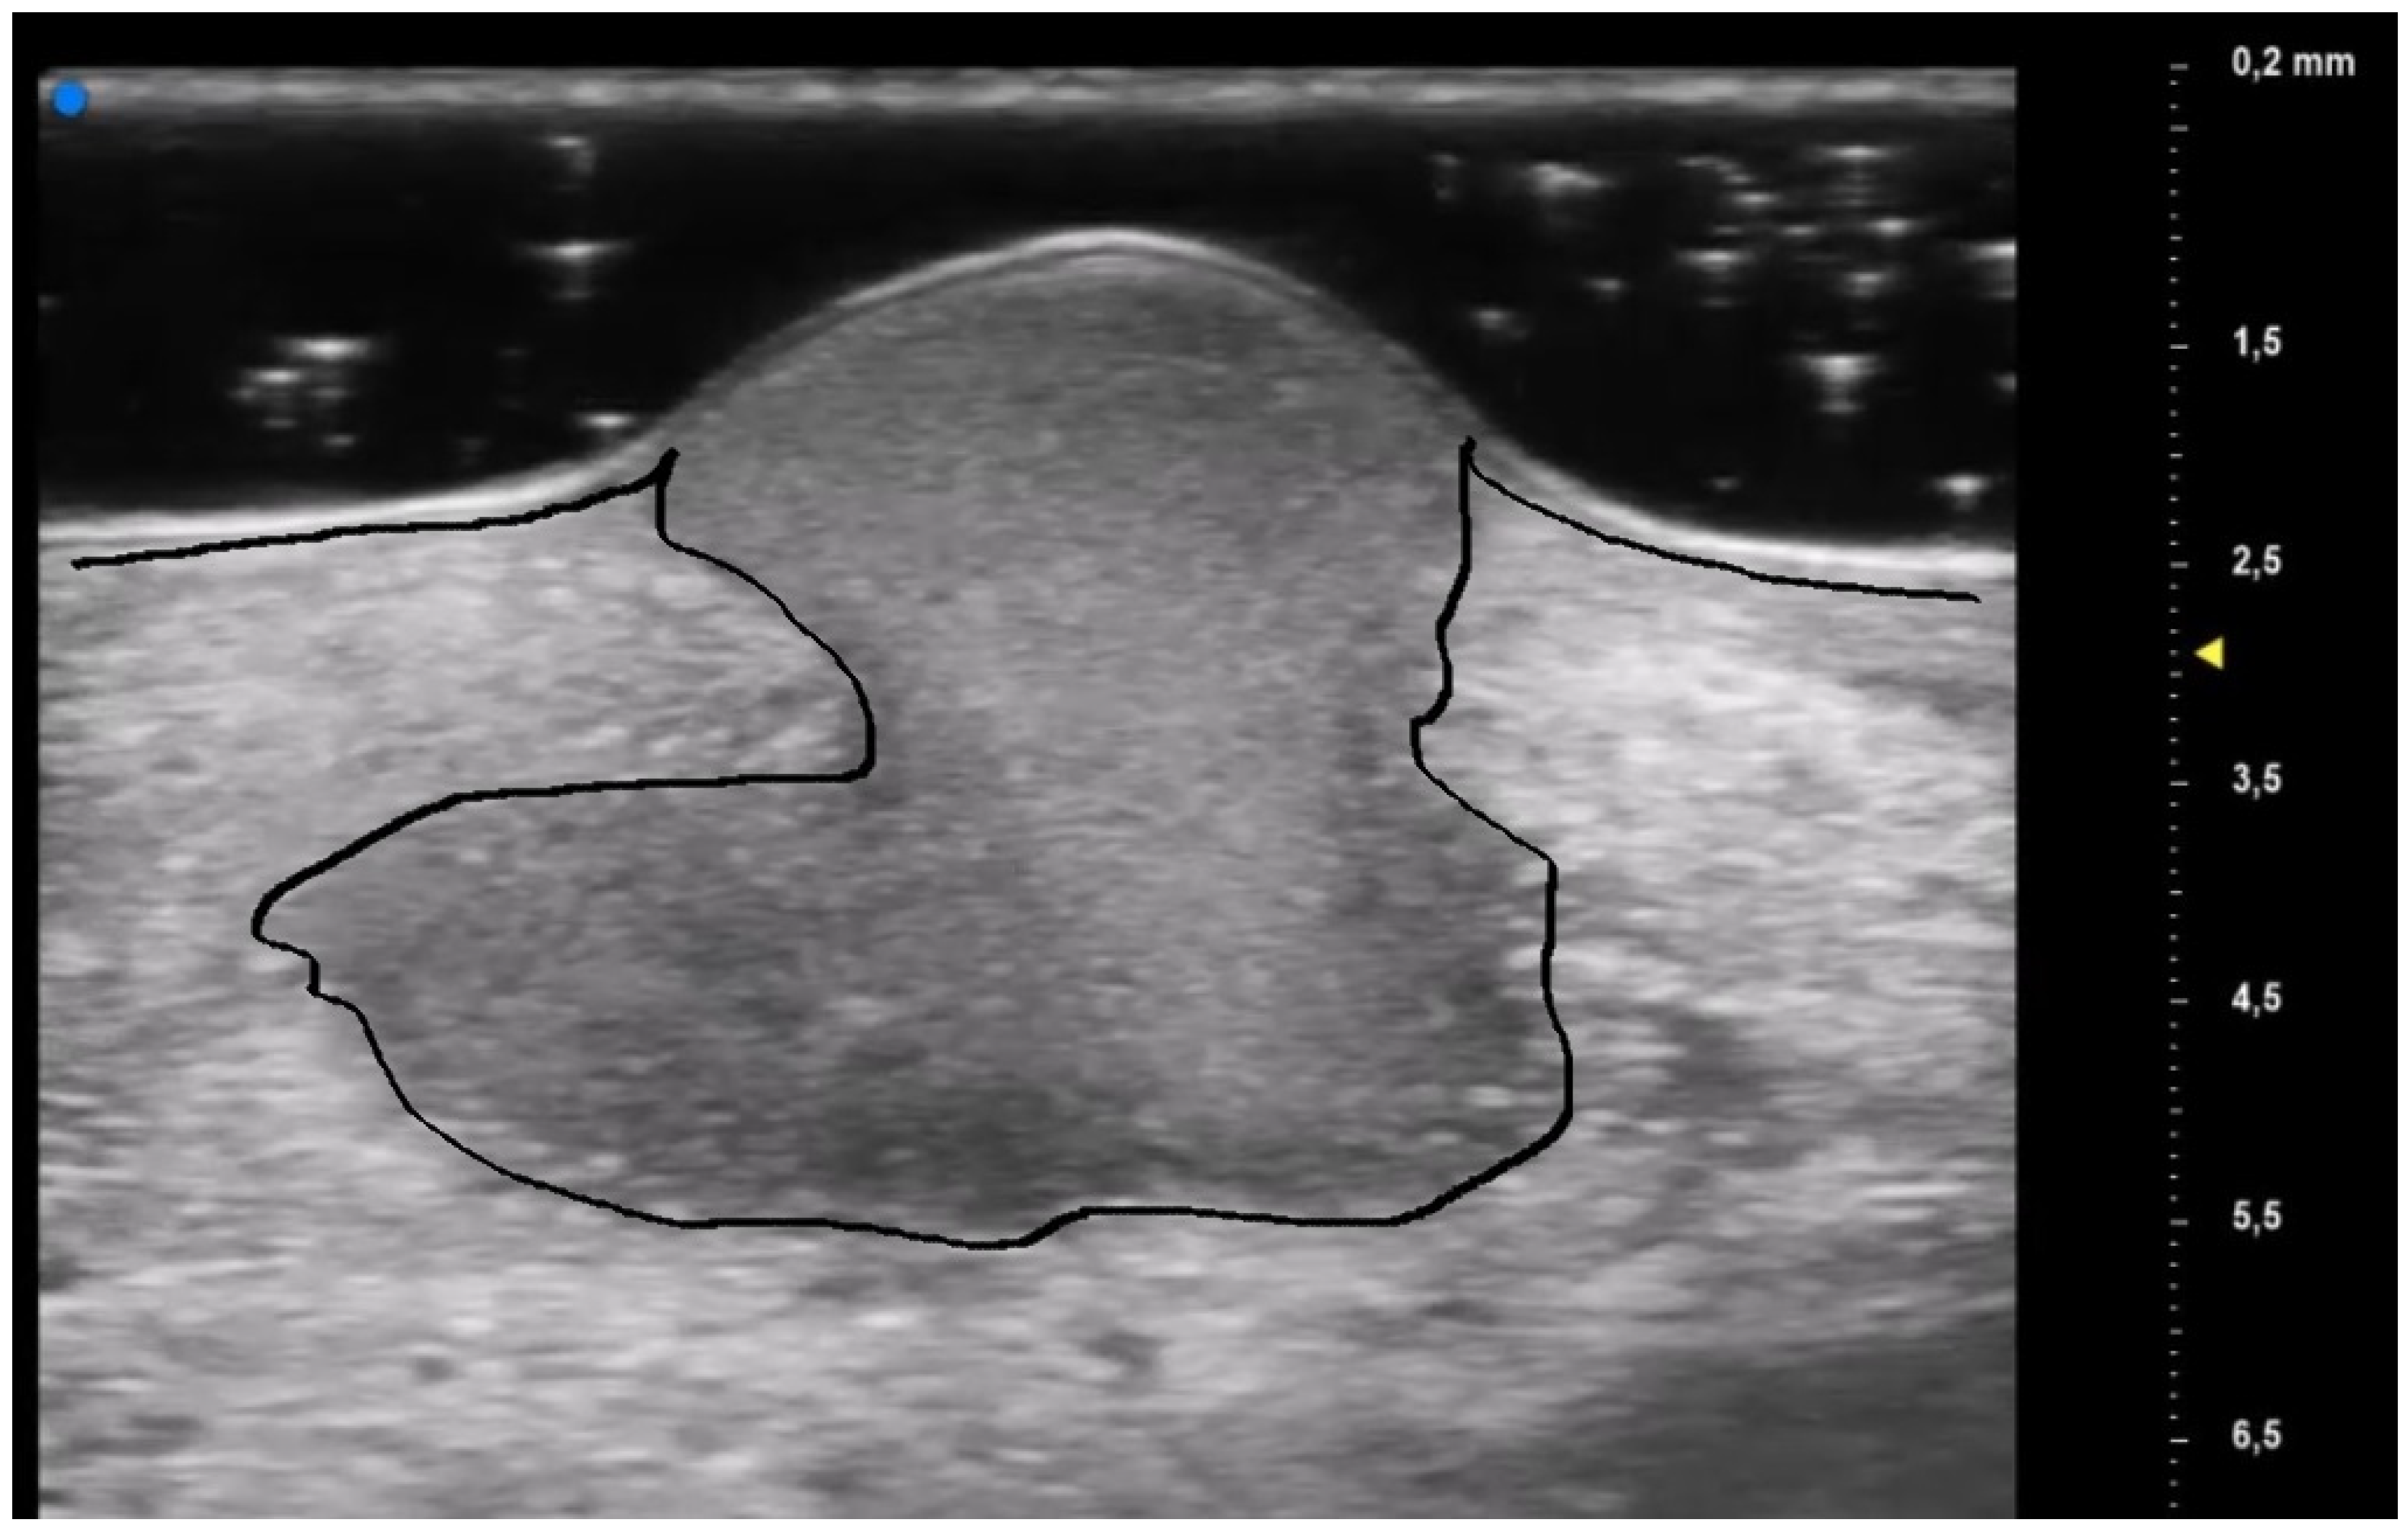

These US findings spared the epidermis and were well demarcated from the surrounding dermis, thus suggesting a hypothesis of “dermal destruction” that we called “tsunami sign” because of the presence of a US image resembling a wave breaking towards the center of the lesion (Figure 6). In T0, hyperechoic oval structures were mainly located at the level of the lesion edges, near V-shaped and U-shaped blood vessels, where the inflammatory response presented a higher activity. Particularly, in T0 an increased expression of U-shaped vessels compared to V-shaped vessels was detectable. In contrast, T1 was characterized by a more uniform vascularization with a significant reduction in U-shaped vessels (p-value < 0.05). These UHFUS findings could be explained by the increased dermal oedema in T0, which resulted in surrounding connective tissue compression and morphological blood vessels changes.

Figure 6.

Early PG lesion: the purulent material (included by the black line) is well demarcated and undermined from the surrounding dermis giving a wave-like appearance, the so-called “tsunami sign”.